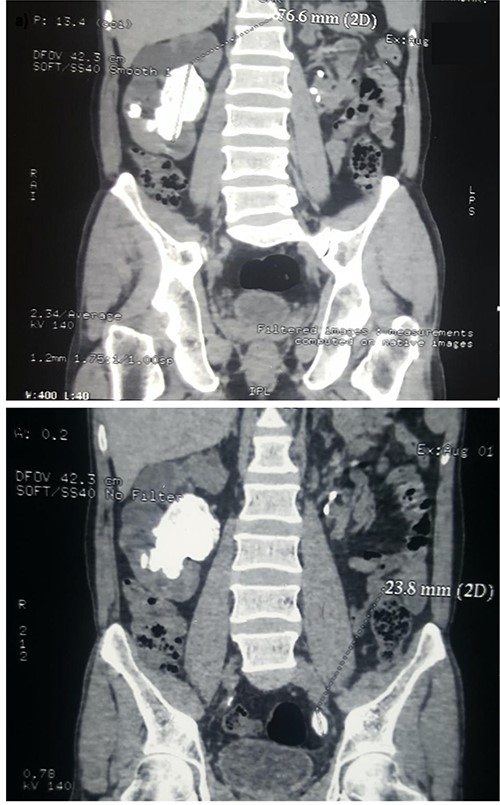

Ultrasound of the kidneys, ureters and bladder (USS KUB) revealed a 2 cm calculus in the left lower ureter with proximal hydroureteronephrosis along with an incidental giant SC, measuring ~8 cm in its largest dimension, occupying the right renal pelvicalyceal system. The SC was surrounded by multiple smaller calculi. A plain X-ray KUB confirmed these findings (Fig. 1). Because of the complexity of this case, a non-contrast computed tomography (NCCT) of the abdomen was performed to further demarcate the anatomy for perioperative planning (Fig. 2a and b).

Coronal view of a non-contrast CT scan demonstrating (a) a 77.6 mm staghorn calculus occupying the right renal pelvis, surrounded by smaller calculi and (b) a 23.8 mm solitary calculus in the left distal ureter.